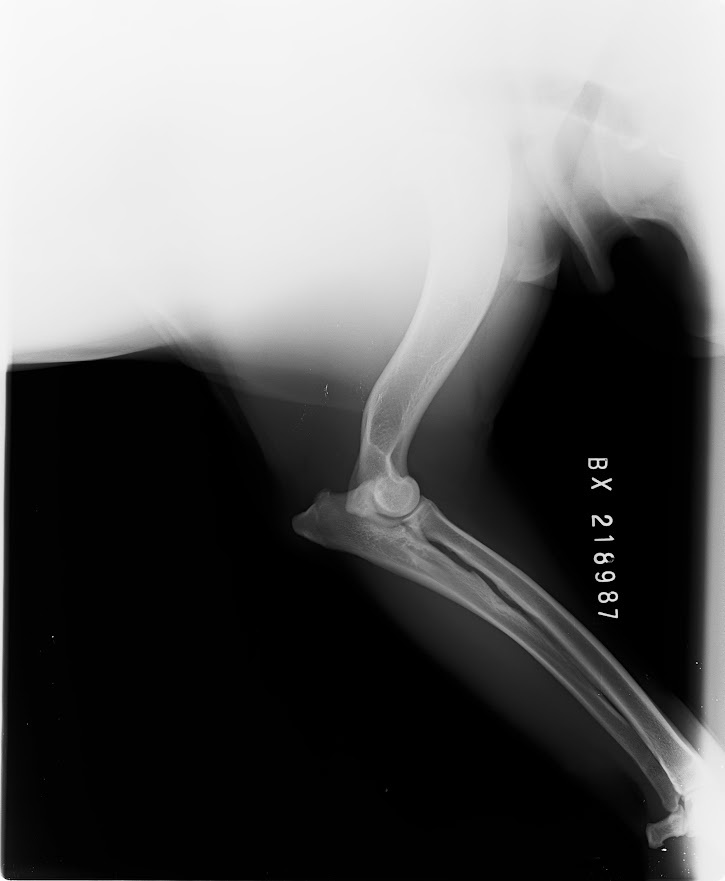

Hledáme nevěstu pro mladého psa BD s PP, Butch Coolidge dei Mastini del Goya, import Itálie, DKK AA, DLK 00, srdce OK, vyšetření sperma, vynikající pohyb, V1, CAC, Národní vítěz ČR, stáří 3 roky, perfektní povaha